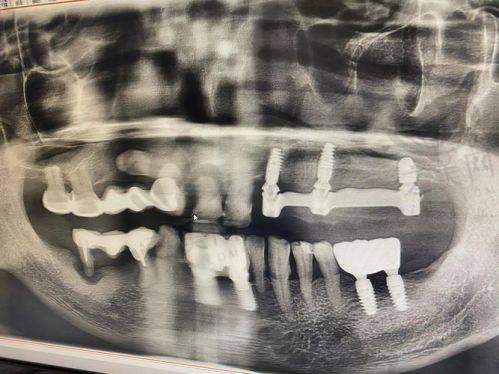

设备与技术方面,医院引进了国内外精良的牙科设备,更新换代也特别及时。采用数字化口腔诊疗模式,像口内数据CT扫描提取、数字化分析及建模等技术,提高了诊疗的精细度和效率。

专科排名上,在种植牙、牙齿矫正、牙齿美容等领域表现出色。拥有专精的种植医生团队和数字化种植中 心,能提供个性化的种植牙服务;擅长多种矫正技术,能满足不同患者的需求;牙齿美容方面经验多、技术精良。

该店有不少特色项目。比如自锁托槽,球面自锁托槽矫正球形外观,圆润不磨嘴,受力均匀,能降低牙套脱落风险。隐形矫正融合了3D打印和电脑三维辅助设计技术,可自由摘戴,方便清洁口腔。舌侧矫正作为新兴正畸技术,矫正器安装在牙齿舌侧面,外观美观。美国3M树脂补牙硬度高、美观、边缘密合,色泽接近天然牙。3D微创种植牙利用数字技术,当天就能完成缺牙修复,修复过程可视化。All - on - 4种植技术针对全口半口无牙情况,利用4颗种植体就能完成口腔种植修复。